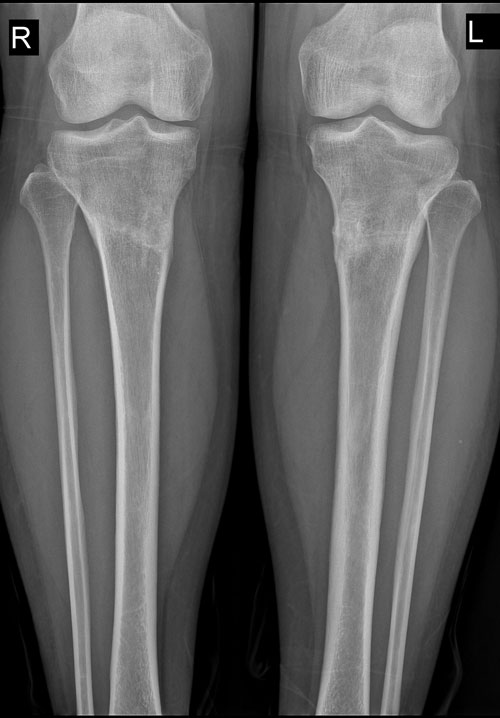

Приветик всем форумчанам!_______________________________________________________________________________________________Николай Николаевич, Наталья добрый вечер! Как поживаете? С Наступающим Новым годом! Взяла сухофрукты--завтра постараюсь отправить через проводника. Позвоню Маришке--она встретит и передаст Вам. Примите маленький южный привет от счастливой обладательницы новых шикарных ножек. Сегодня ровно месяц со снятия аппаратов. Отправляю фото ножек, а в январе сделаю и отправлю рентген.